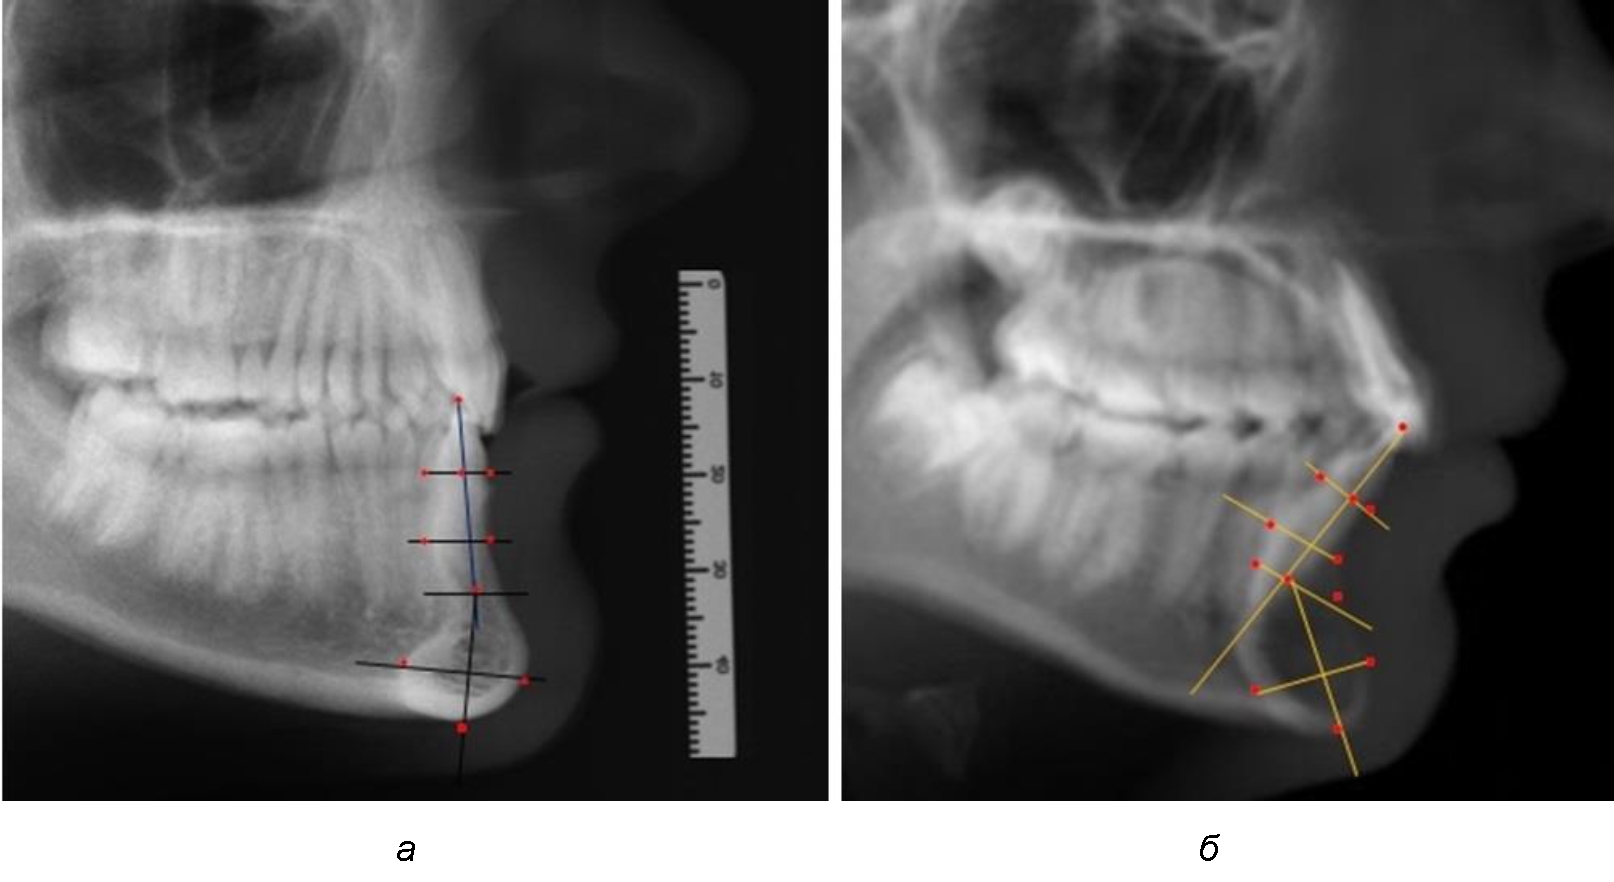

При анализе боковых телерентгенограмм использовали фрагменты гнатической части, на которых оценивали вертикальные и сагиттальные параметры резцового нижнечелюстного сегмента, на который наносили те же ориентиры, что и при анализе нативных препаратов и их рентгенограмм.

При необходимости и/или возможности проведения КЛКТ-исследования проводили анализ с сопоставлением фрагмента, что повышало точность диагностических мероприятий (рис. 2).

Рис. 2. Фрагменты ТРГ с ориентирами для измерения параметров резцового сегмента (а) и с наложением фрагмента КЛКТ (б)